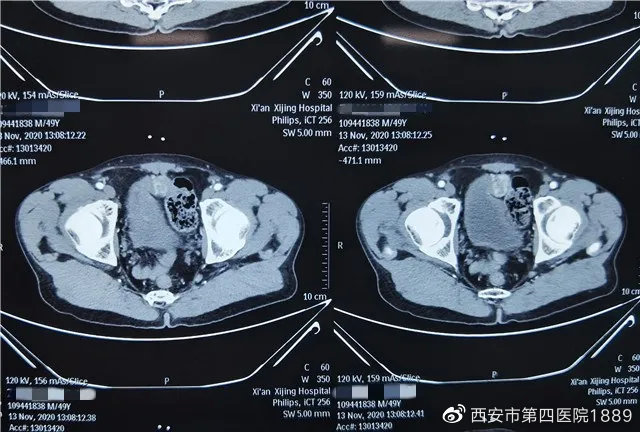

一次偶然的机会,张先生来西安进行检查,外院膀胱镜检查未见异常,超声检查报告结果:膀胱前方实性结节、血运丰富,无法确诊,建议活检。后几经辗转,于11月20日,来到了西安市人民医院(西安市第四医院)航天城院区泌尿肾脏病院就诊。泌尿肾脏病院的薛庆副主任医师仔细询问病史,并详细对患者进行了查体后,综合考虑为肿瘤。住院后进行CT检查,结果显示为膀胱前壁占位约2cm大小,考虑恶性肿瘤,需行手术治疗。

真相大白!病理检查结果是副神经节瘤,属于内分泌功能的肿瘤一种,符合薛庆副主任医师的前期判断。